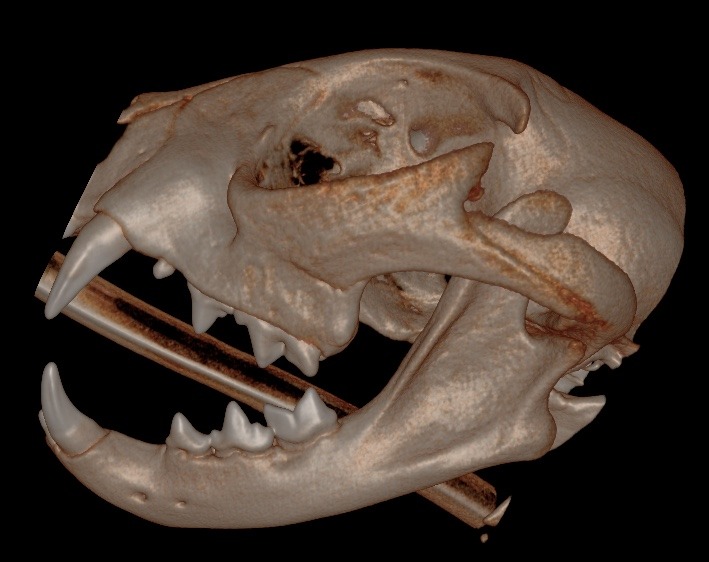

A cat presented with a temporomandibular joint (TMJ) luxation after a fall from a shelf. Initial attempts to reposition the TMJ at an emergency clinic were followed by a referral to ensure no fractures. The treatment involved the 'button' technique for TMJ stabilization, which was successful after three weeks of esophageal tube feeding. Post-treatment, the cat returned to normal function, although slight TMJ mobility and subluxation were noted. Imaging confirmed no fractures, and Ethilon with 3 buttons was used for stabilization, to be removed in 7-14 days. Follow-up imaging, specifically Cone Beam Computed Tomography (CBCT), was recommended one year later to monitor dental development.